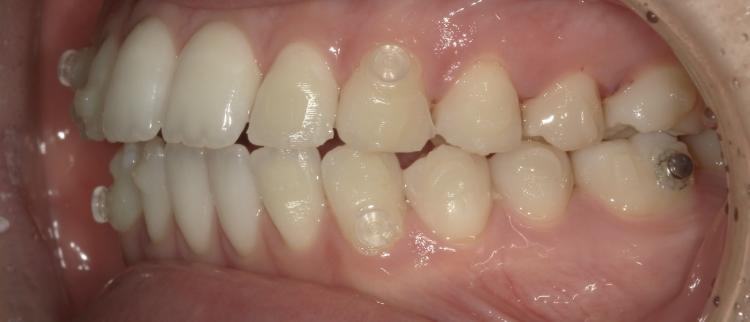

以下の写真はマウスピース矯正をはじめる前と現在の歯並びを比べたものです。

前歯の前突感がなくなりました!歯並びが変わるので噛み合わせにズレが出てくるのですが最後に噛めるように調整するので安心できます。